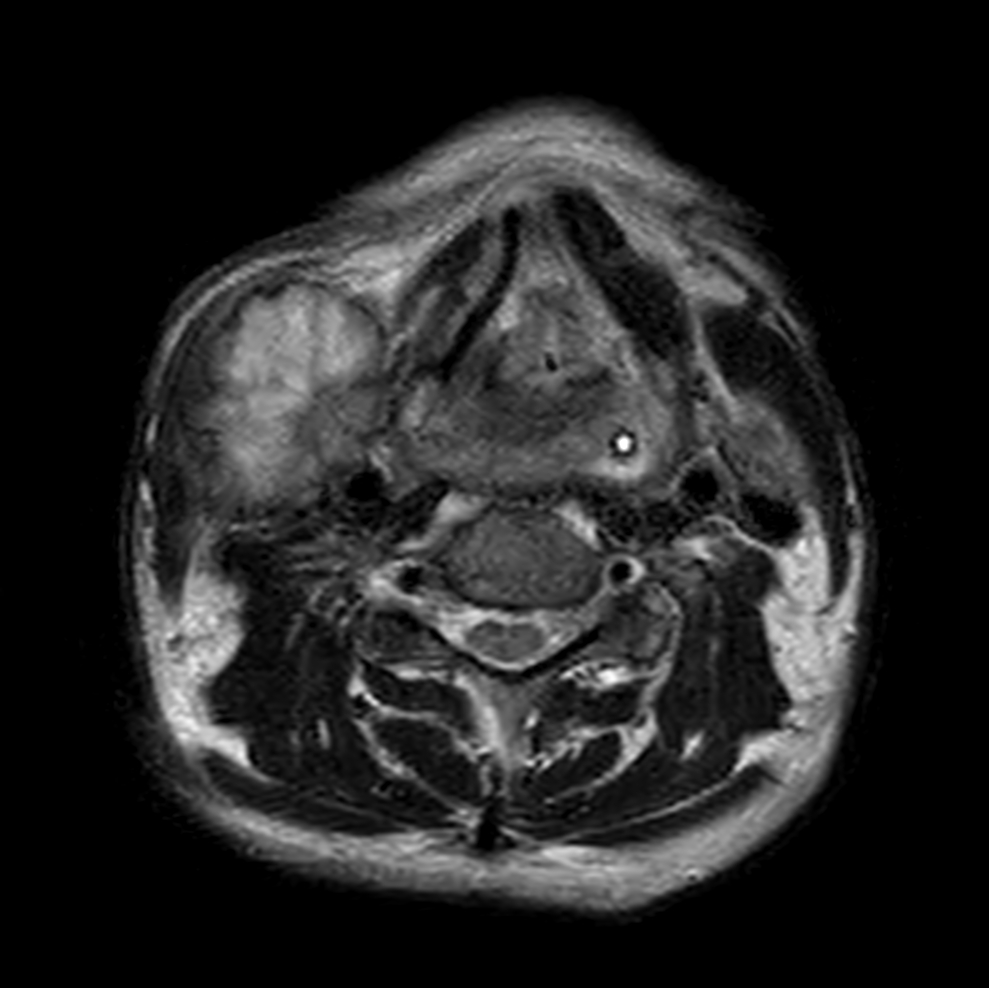

Axial T2w TSE

Axial STIR TSE